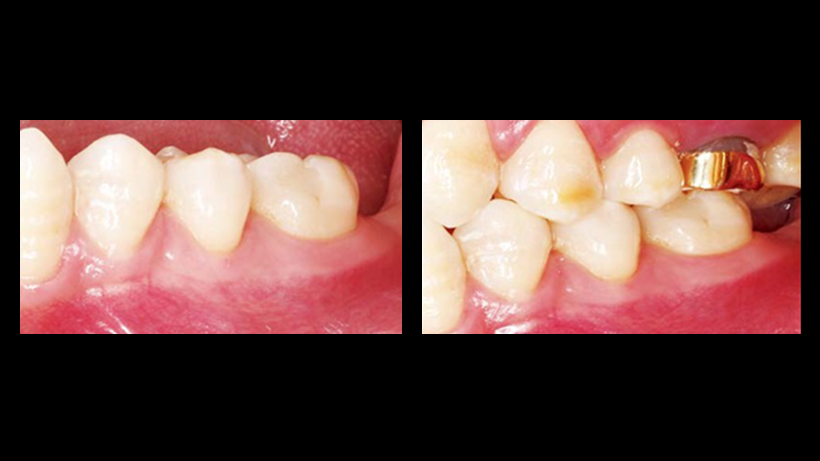

Clinical case: Immediate post-extraction insertion of implant & immediate loading

- Courtesy of Prof. Giuseppe Luongo, Italy -

AnyRidge, immediate loading, single implant, multicenter study, maxillary anterior, Prof. Giuseppe Luongo, single replacement

Products:

AnyRidge implant system

Immediate functional loading of single implants: a multicenter study with 4 years of follow-up

/J Dent Res Dent Clin Dent Prospect 2018; 12(1):26-37 | doi: 10.15171/joddd.2018.005

https://www.ncbi.nlm.nih.gov/pubmed/29732018